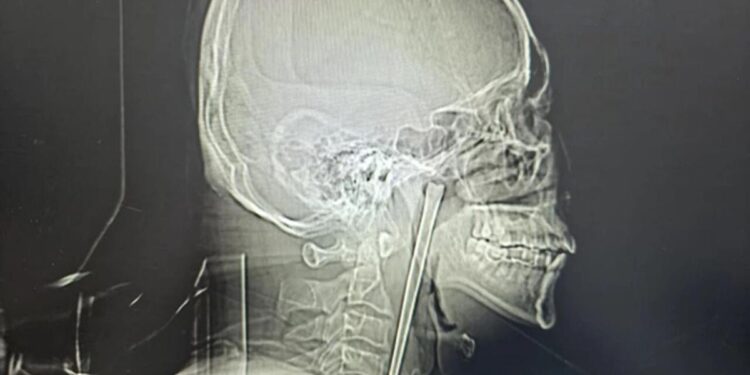

A man in China swallowed a metal chopstick while eating dinner eight years ago and decided to leave it lodged in his throat until a surgeon finally removed it last month, March 2026.

According to a jaw-dropping hospital case study published in March, the “alcoholic” patient, identified only as Mr. Wang, went in for a check-up shortly after gulping down the five-inch utensil in 2018 but refused to have it removed.

Wang, 46, didn’t want doctors to cut his neck open at the time, so he lived with the discomfort for years, the South China Morning Post reported.

Surgeons performed a minimally invasive operation to remove the obstructive object via Wang’s mouth instead of slicing open his neck, according to the hospital’s report.